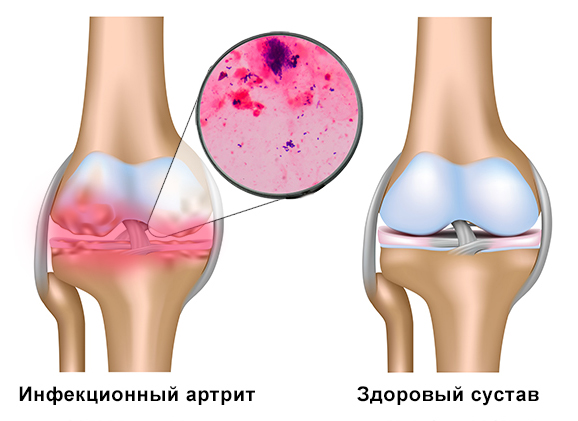

Медицинские состояния: Септический артрит коленного сустава

Раздел: Мир в картинках